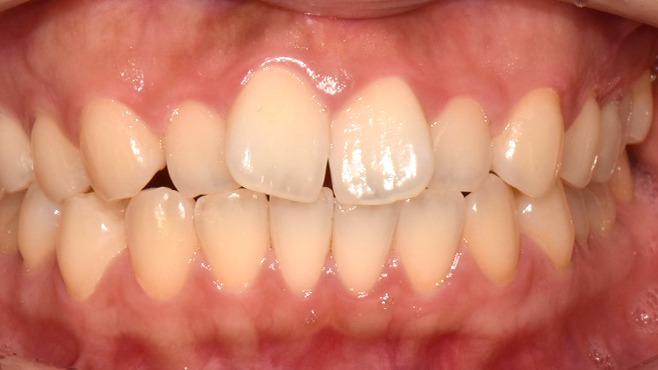

before

after

※ 위 임상사진은 동일조건으로 촬영되었으며, 사진에 대한 별도의 조작이 처리되지 않았습니다.

※ 위 임상사진 및 포트레이트는 환자와의 포괄적인 초상권 계약 이후 사용하고 있습니다.

※ 수술 및 치료과정에서 부작용이 발생할 수 있으므로 충분한 상담과 신중한 판단이 요구됩니다.

실제 치료 사례

수많은 환자들이 고민 끝에 선택한 치료,

그리고 그 후의 놀라운 변화

- ※ 위 임상사진은 365서울원탑치과에서 진료를 시작하고 마친 동일한 환자의 사진입니다.

- ※ 위 임상사진은 동일한 장소에서 동일한 조건으로 촬영되었으며, 사진에 대한 별도의 조작이 처리되지 않았습니다.

- ※ 수술 및 치료 과정에서 부작용이 발생할 수 있으므로 의료진과의 충분한 상담과 신중한 판단이 요구됩니다.